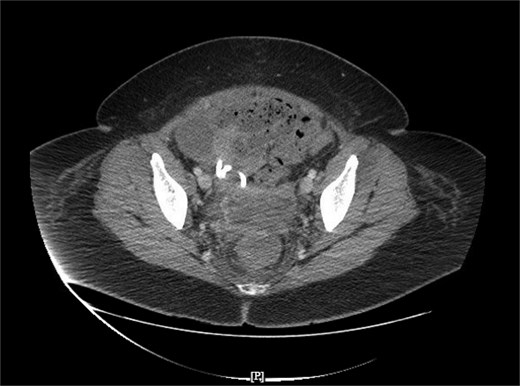

To ameliorate the bleeding risks of tPA-dornase, anticoagulation was decreased from therapeutic to prophylactic lovenox dosing. The patient received an infusion of 10 mg alteplase in 30 ml normal saline followed by 5 mg dornase in 30 ml normal saline via the IR drain. The drain was clamped for 1 h, and the patient was encouraged to ambulate while the drain was clamped. An hour afterward, the drain was unclamped, and the drainage was monitored for character and volume. Hemoglobin was trended to ensure laterality. The patient underwent a total of five tPA-dornase infusions over 5 days and tolerated the infusions well without signs of bleeding (Table 1). A CT scan was performed after the final infusion, showing resolution of the pelvic fluid collection (Fig. 4). Antibiotics were discontinued, and the patient was discharged after 10 weeks inpatient. At follow-up, the patient had no recurrent signs and symptoms of recurrent abscess.

Resolution of pelvic fluid collection with 12 Fr catheter in place, in the axial view.